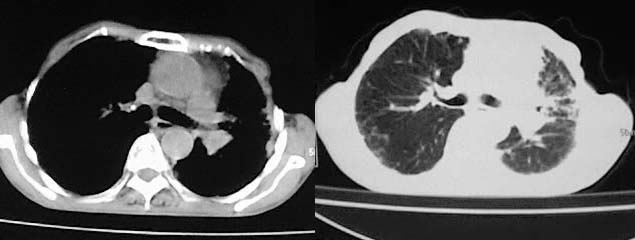

以下是引用有风的日子在2008-5-2 12:13:00的发言:[br][emb10][br][br]肺ca?有病理支持吗?[br][br]我看更象是肺tb并支扩、间质性肺炎。最好拿个病理结果来,不然这点影像资料诊断肺ca是难以服人的![br][br]至于主动脉瘤的诊断问题,国外认为≥4.0cm就可诊断了,国内对此诊断标准更为严格。患者升主动脉明显增粗,即>4cm。你诊断个升主动脉扩张并不为过!

以下是引用zjzjr在2008-5-2 14:39:00的发言:[br]支持双侧继发型肺结核,左侧胸膜肥厚,慢性支气管炎伴间质纤维化.